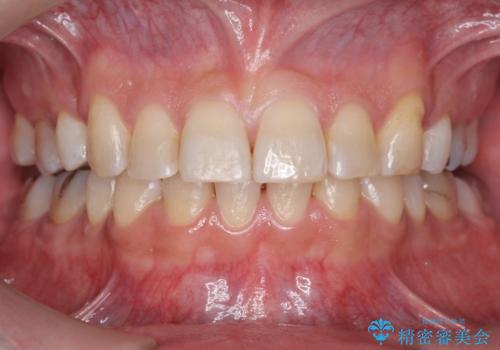

[インビザライン] 前歯のガタつき・すれ違い マウスピース矯正治療

![[インビザライン] 前歯のガタつき・すれ違い マウスピース矯正治療の症例 治療前](https://seimitsushinbi.jp/wp/wp-content/uploads/2021/08/0b21121c07cfd741f7e6e7110f2c1705-500x350.jpg?v=1629705726)

![[インビザライン] 前歯のガタつき・すれ違い マウスピース矯正治療の症例 治療後](https://seimitsushinbi.jp/wp/wp-content/uploads/2021/08/IMG_3357-500x350.jpg?v=1629705763)